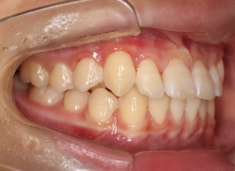

治療前